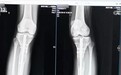

据央视报道,医生通过拍X片发现,这名22岁的患者双小腿做了增高手术,骨折断端没有完全愈合好,手术部位的皮肤有炎症反应。

据了解,“断骨增高手术”又称“肢体延长术”。是根据肢体组织在一定的力量刺激下可以再生的原理,把小腿或大腿的骨头“断开”,然后在体外安装具有牵伸作用的外固定支架,每天不超过1毫米的速度,将肢体缓慢延长到满意的长度。

专家介绍,在实施断骨增高手术时,外固定“增高器”的钢针要穿透患者的双腿,可能损伤腿部的血管、神经组织,造成感染,甚至引发骨髓炎,造成残疾。